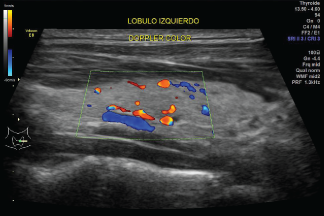

Ecografía Doppler Color

Las imágenes del ultrasonido son capturadas en tiempo real; eso es, no sólo muestran la estructura de una parte en particular del cuerpo, sino que también pueden mostrar el movimiento de los órganos internos así como el flujo de sangre a través de los vasos.

El doppler color permite precisar la dirección del flujo y distinción de una vena de una arteria, es necesario evitar presión sobre la mama para evitar compresión de los vasos, se necesita ajustar parámetros que permiten obtener óptima coloración en los vasos, filtro de pared lo más bajo posible, algoritmo adecuado para eliminar artefactos de movimiento, máxima ganancia.

Los ultrasonidos Doppler son importantes en el diagnóstico de lesiones mamarias porque un tumor maligno (canceroso) de masa puede tener irregularidades del flujo sanguíneo.